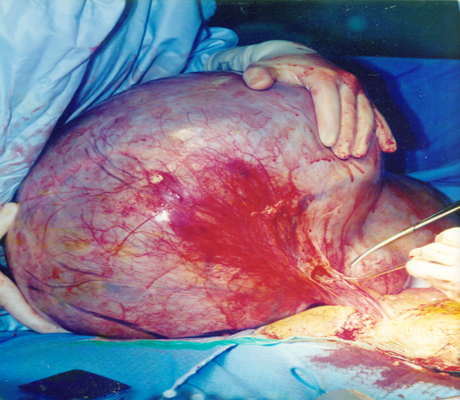

Pelvic Mass

Examples of some pelvic masses dealt with by open surgery.

This is a big ovarian tumour (cancer) that was removed through open surgery.